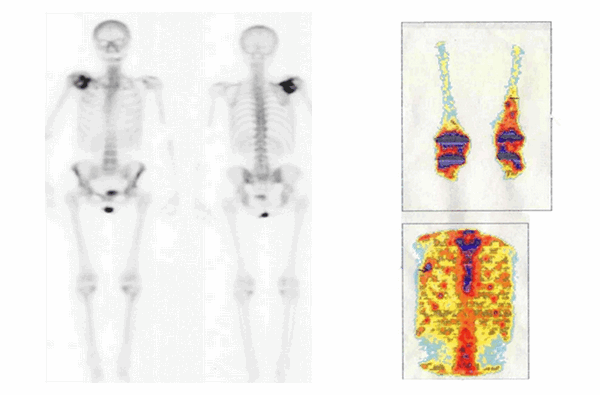

Сцинтиграфия скелета уже долгое время остается стандартным методом диагностики костных поражений, являясь более чувствительной, чем рентгенологические методы. Она позволяет проводить исследование всего тела человека за небольшой промежуток времени. Данное исследование основано на повышении накопления фосфорных соединений в очаге поражения, что свидетельствует об активности процесса, характерного для злокачественных новообразований (рис. 3).

Рис.3. Патологическое накопление радиофармпрепарата (Технеций mTc)